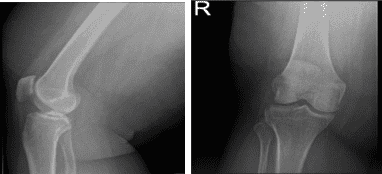

Right Knee X-ray AP Lateral and Oblique

MRI-3T Right Knee Non-contrast

MRI results were presented and shown that there is a radial tear through the posterior horn of the medial meniscus. Tricompartmental cartilage loss, worst in the medial compartment where there is a focal full-thickness chondral defect. There is moderate partial-thickness patellar cartilage loss. Small joint effusion and Baker’s cyst.